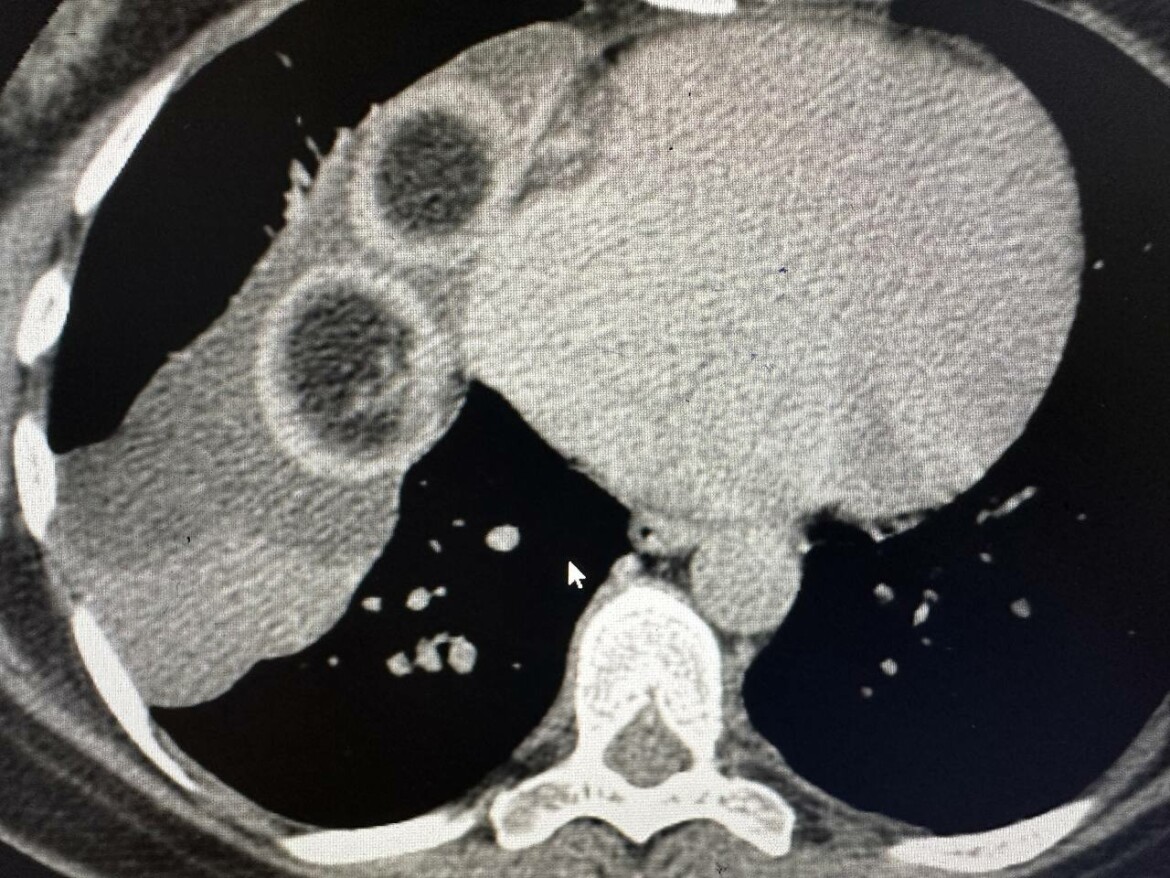

Образование заметили у 44-летней жительницы Бавлинского района республики на флюорографии, на КТ подтвердили. Киста расположилась в средостении – это центральное пространство грудной клетки между двумя плевральными полостями. Женщину направили в РКБ.

«Оказалось, что рядом с сердцем выросла дермоидная киста размером 10 на 7 на 15 сантиметров. Внутри этой кисты образовались две большие волосяные головки», – рассказали в РКБ.